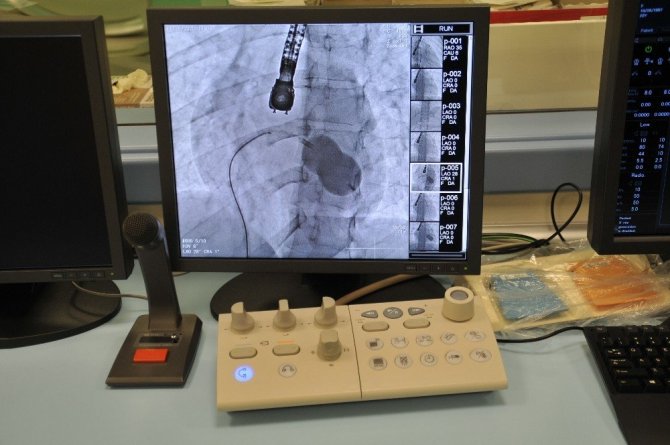

Eskişehir Şehir Hastanesi'nde ilk defa mitral balon operasyonu yapıldı. Operasyon, anjiyografi cihazı ile adım adım kaydedildi.

Eskişehir Şehir Hastanesi'nde Kardiyoloji Uzmanı Dr. Mehmet Özgeyik ve 4 kişilik ekibi tarafından ilk defa mitral balon operasyonu yapıldı. Türkiye'de az sayıda yapılan kalp kapağı balon işlemiyle yeni anne olmuş genç bir hasta sağlığına kavuştu. Bu sayede hastalar ameliyat olmaktan, ömür boyu kan sulandırıcı ilaçlar kullanmaktan ve metal bir kalp kapağı ile yaşamaktan kurtuluyor.